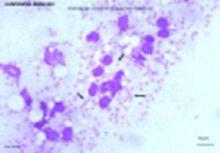

白蛉以頭部的喙器刺入皮膚吸吮人和動物的血液,被叮咬後有人可毫無反應,有人感微癢或劇癢,局部出現紅色丘疹、風團、小結節或糜爛、水皰等損害,愈後可留下色素沉著的斑片。若白蛉體內含有LD小體在叮咬人的皮膚時可引起利什曼病(黑熱病)、皮膚利什曼病的發生。

⑴黑熱病:又稱內臟利什曼病,病原是杜氏利什曼原蟲。該病分布廣泛,在我國廣大流行區的主要媒介為中華白蛉指名亞種,僅新疆為中華白蛉長管亞種、碩大白蛉吳氏亞種(P.major wui)和亞歷山大白蛉(P.alexandri)。內蒙古和甘肅部分地區為碩大白蛉吳氏亞種。近年來發現在我國川北和隴南山區存在以中華白蛉為主要媒介的黑熱病自然疫源地。